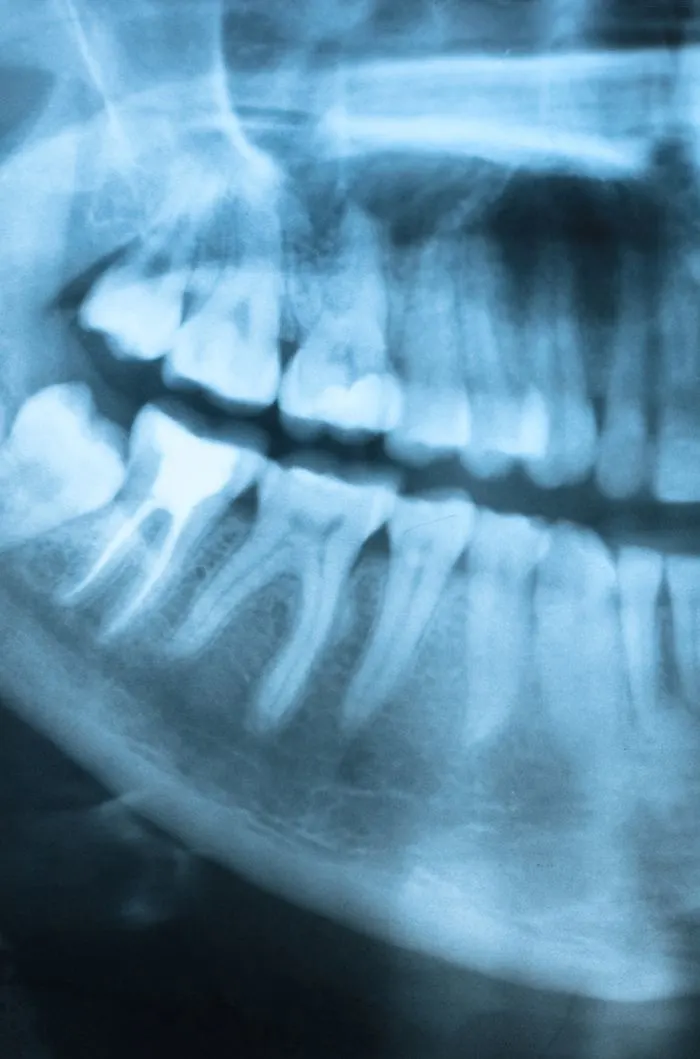

Treatment Plan

During your consultation, we’ll take digital x-rays to assess the condition of your tooth and the surrounding bone. We’ll explain whether extraction is truly necessary and walk you through any alternatives. If you’re moving forward, we’ll review the number of teeth to be removed, aftercare expectations, and any follow-up recommendations for tooth replacement. We’ll answer every question you have so you feel fully informed and know what to expect.